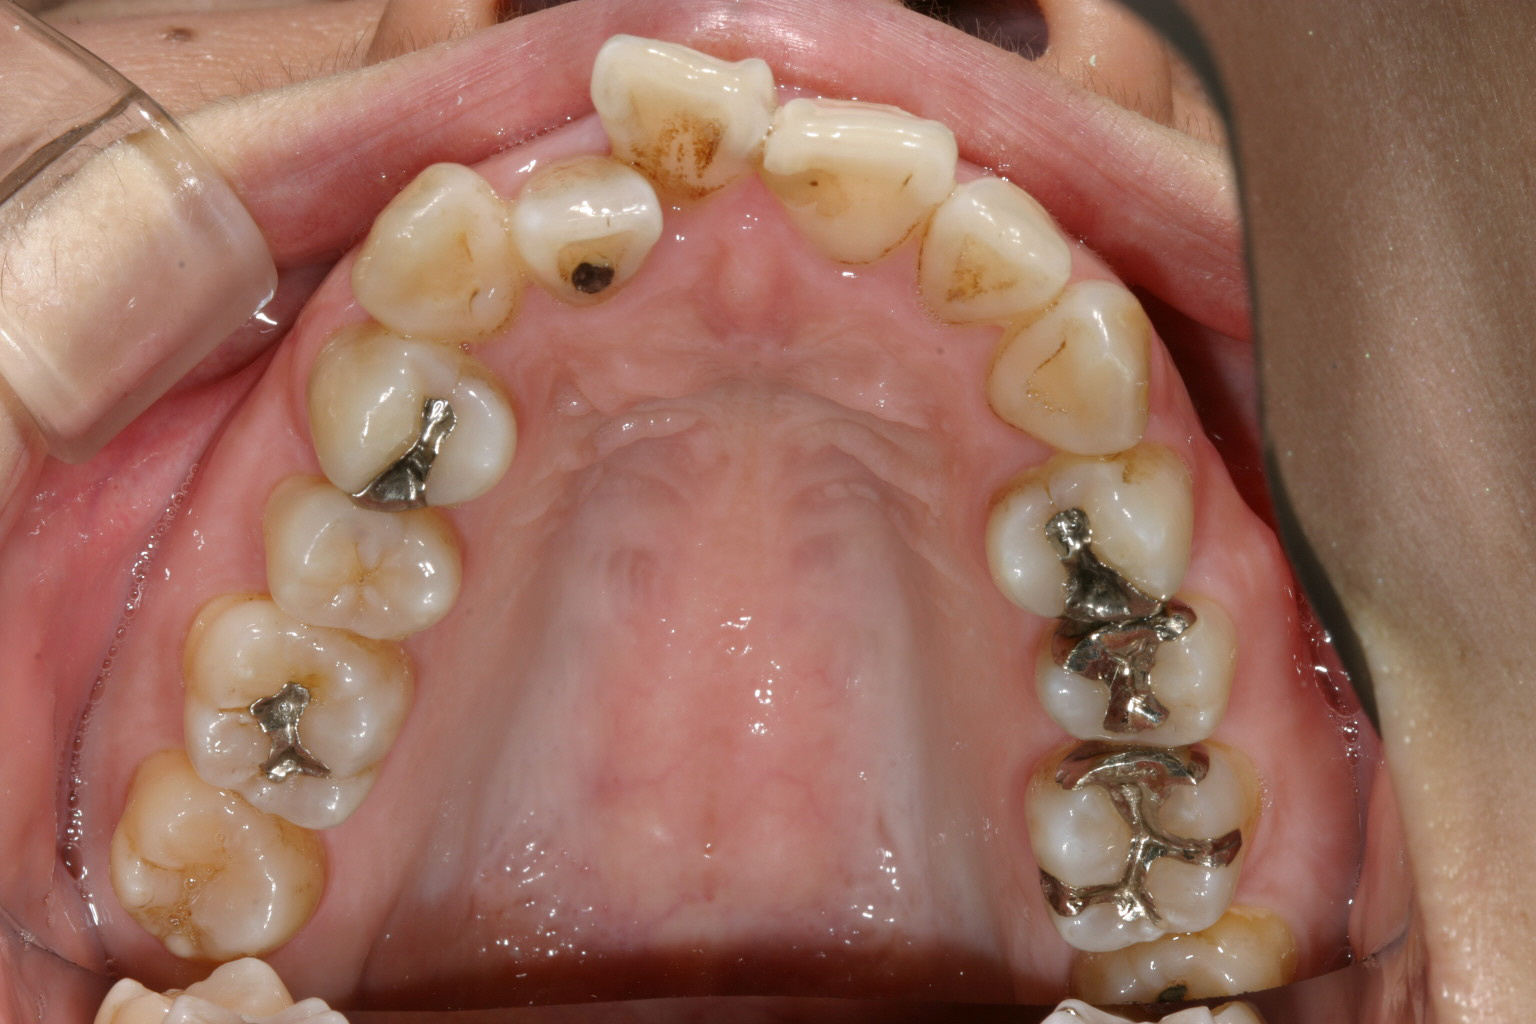

アーチの形状がV字になっている為、犬歯と犬歯の間が狭く前歯がガタガタになっています。

下顎もV字になっています。 又今日臼歯部が左右とも内方に傾斜しています。